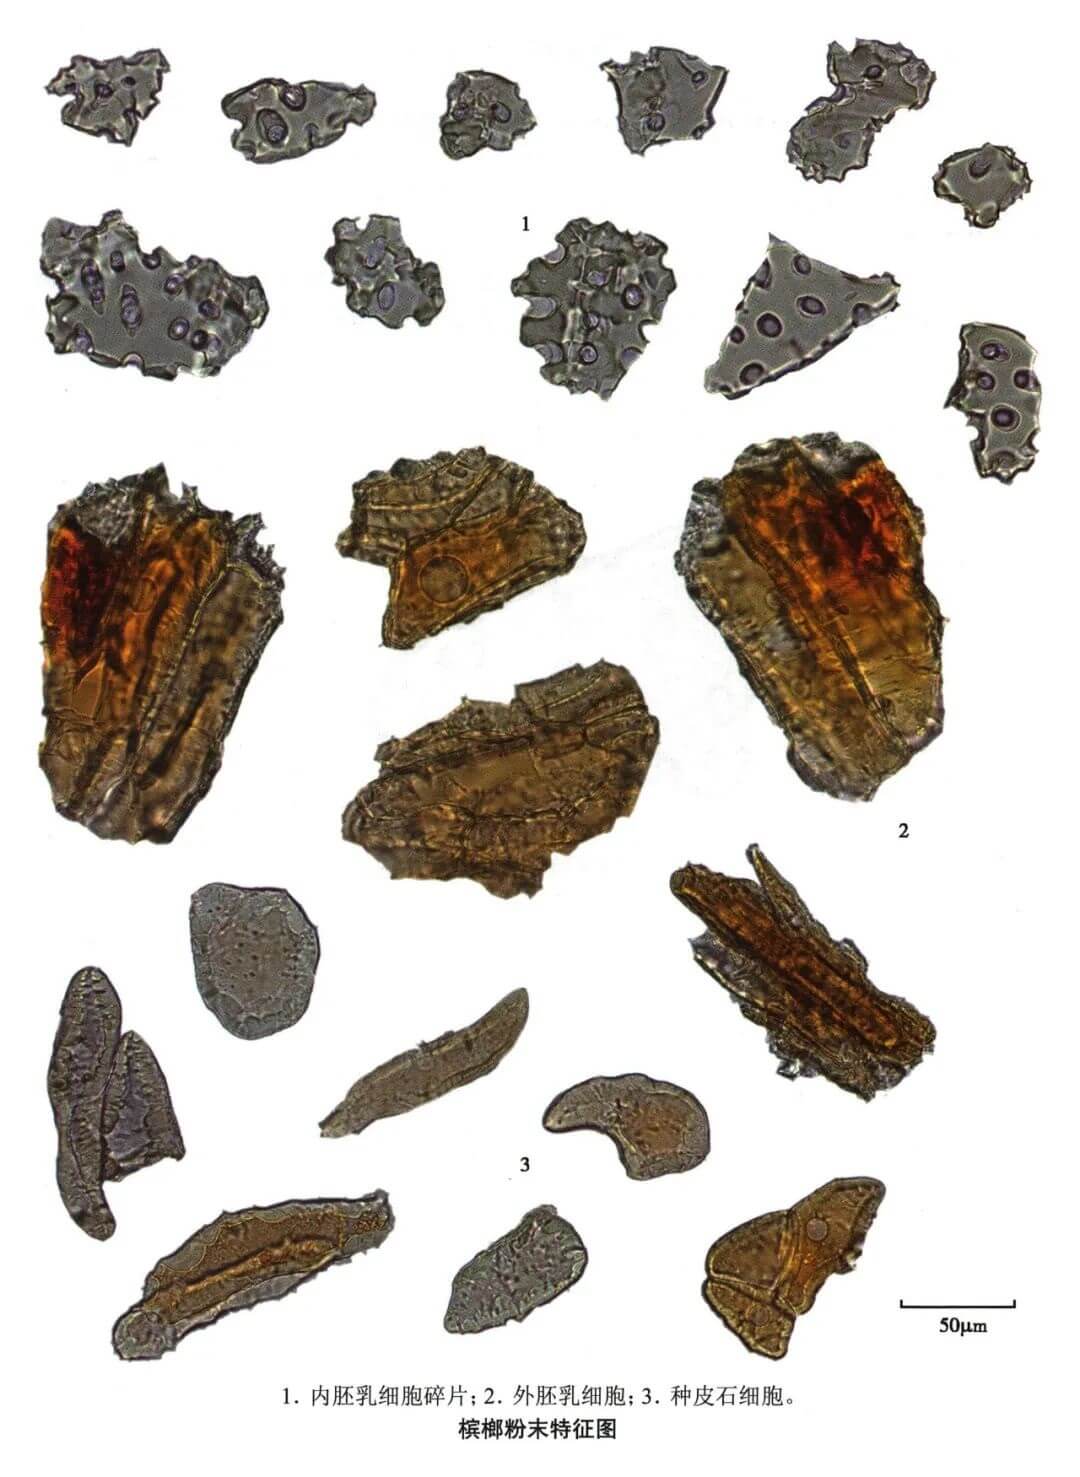

| 【显微鉴别】 粉末红棕色至淡棕色。内胚乳碎片近无色,细胞呈多角形或类方形,壁厚6~11μm,有类圆形大纹孔。种皮石细胞纺锤形、长方形或多角形,直径24~64μm,壁不甚厚。外胚乳细胞长方形、类多角形,内含红棕色或深棕色物。 |

| 【显微重点】 内胚乳有类圆形大纹孔、石细胞。 |

| 【图谱来源】 《中药成方制剂显微图典》 |